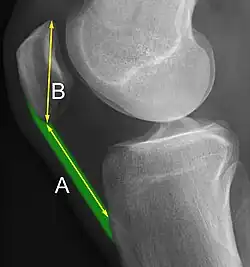

Insall-Salvati ratio (A divided by B).[7]

The Insall-Salvati ratio helps to indicate patella baja on lateral X-rays, and is calculated as the patellar tendon length divided by the patellar bone length. An Insall-Salvati ratio of < 0.8 indicates patella baja.[7]